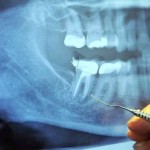

Patite li od degenerativne bolesti? Da li su vam rekli da je “sve to samo u vašoj glavi”? To možda i nije tako daleko od istine… jer se uzrok vaše bolesti nalazi u vašim ustima. Postoji uobičajena stomatološka procedur...